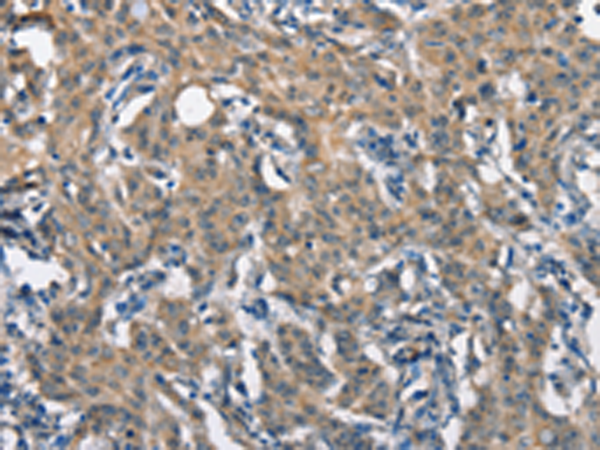

分类: 科研抗体货号: P07338别名: CLA1; SRB1; CLA-1; SR-BI; CD36L1; HDLQTL6应用: IHC反应种属: Human